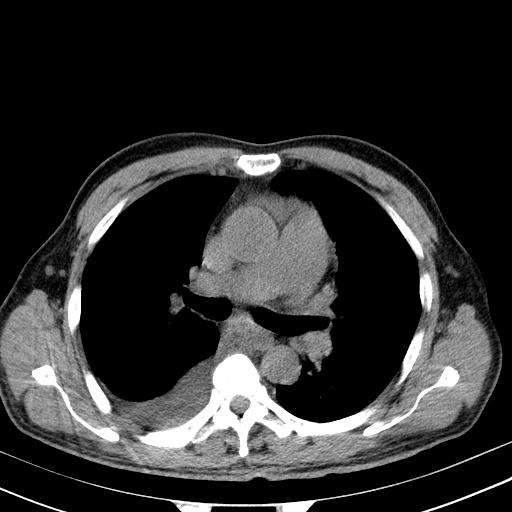

以下是引用zjzjr在2010-3-21 17:39:00的发言:[br]右下中心型肺癌并阻塞性肺炎/不张,纵膈淋巴结肿大,右侧大量胸腔积液,左侧少量胸腔积液

以下是引用zxl51642在2010-3-21 17:06:00的发言:[br]右下中心型肺癌并阻塞性肺炎/不张,纵膈淋巴结肿大,右侧大量胸腔积液,左侧少量胸腔积液,少量腹水。建议纤维支气管镜进一步检查。